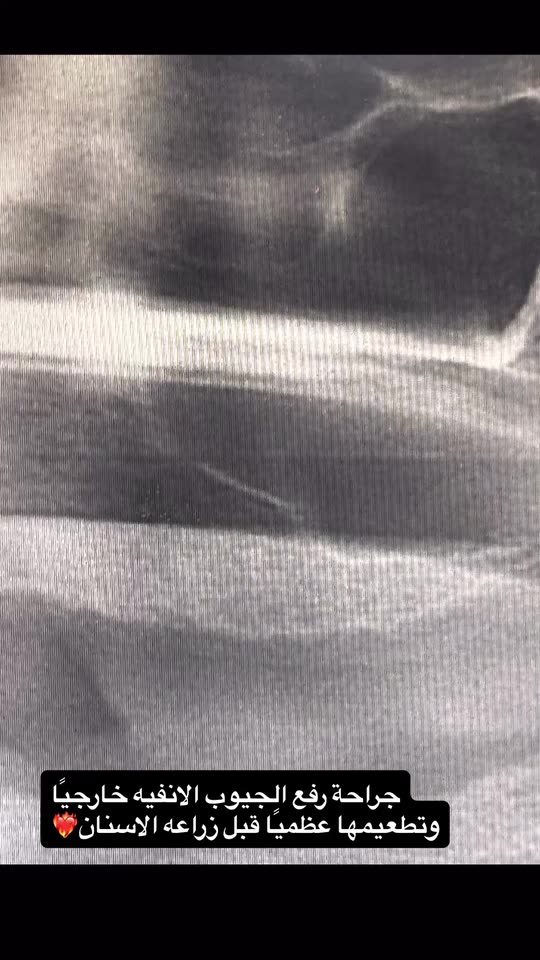

طبيب أسنان-أمراض وجراحة اللثه وزراعة الأسنان🦷